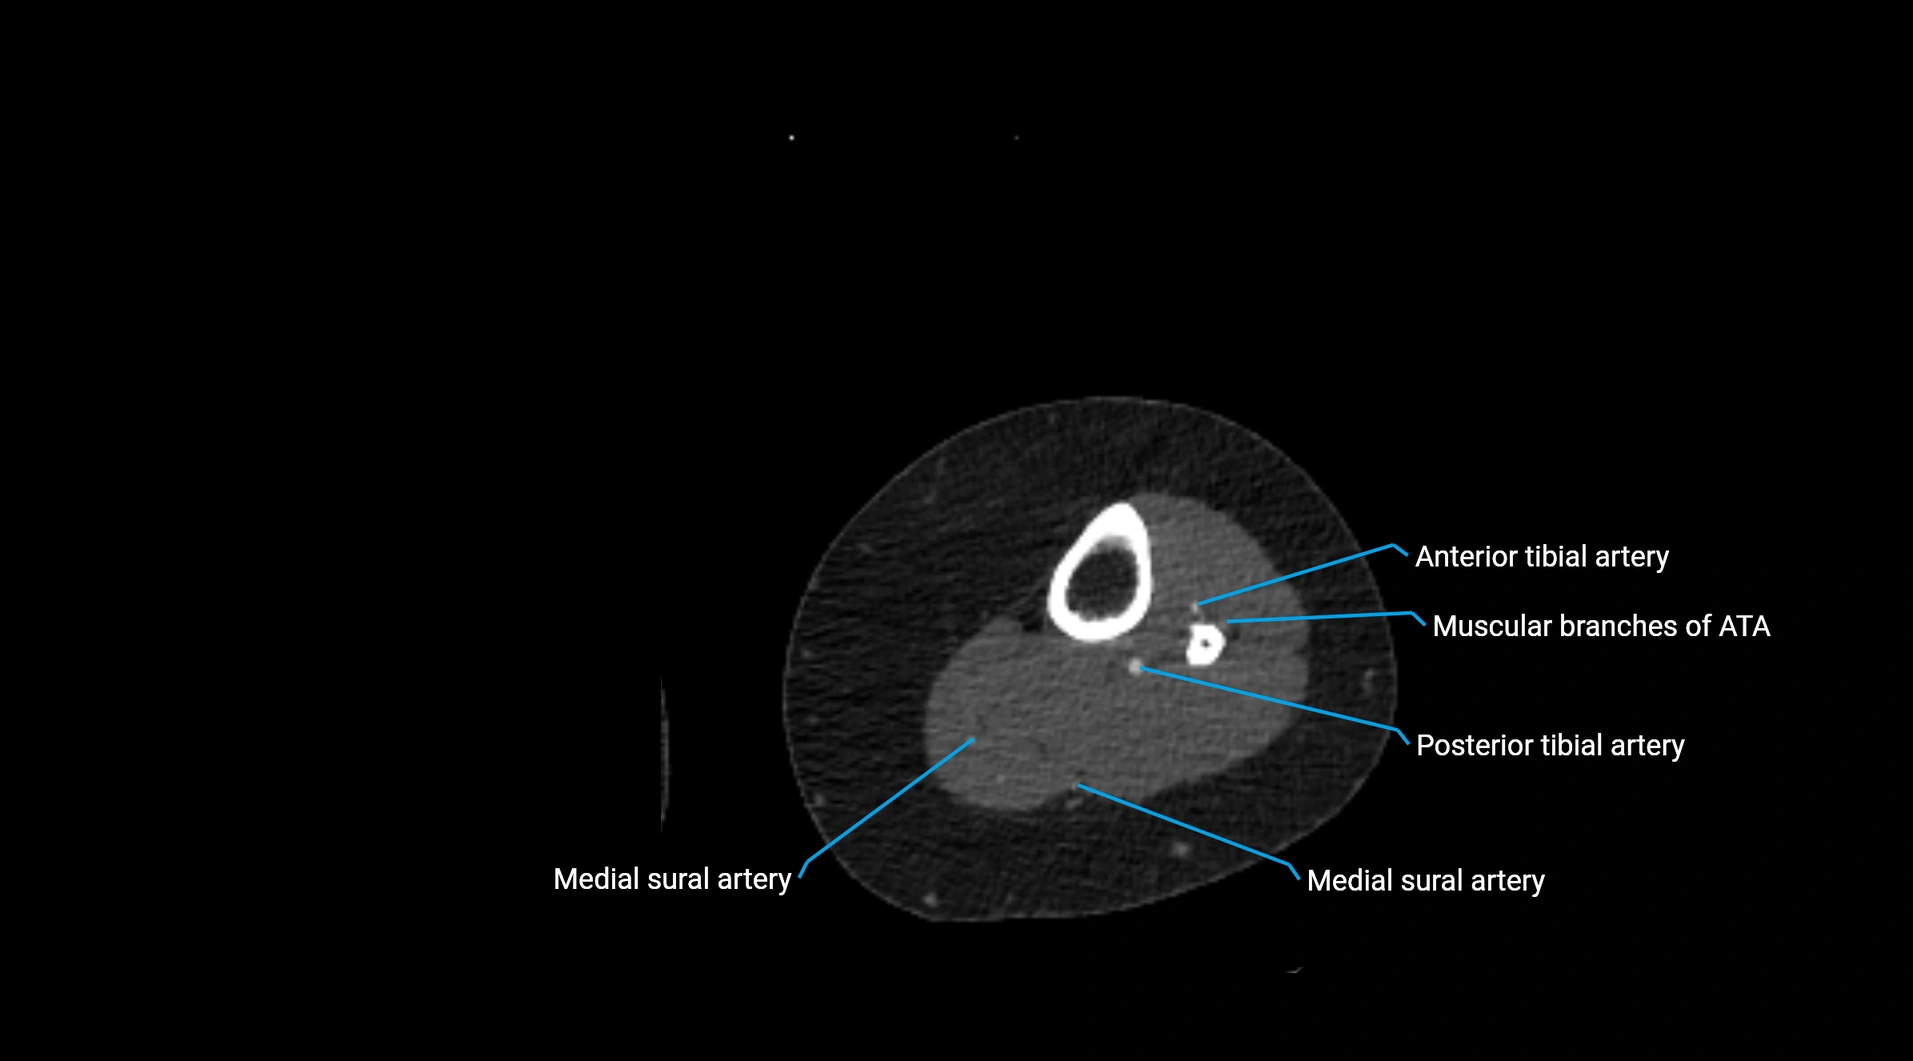

CT images

image